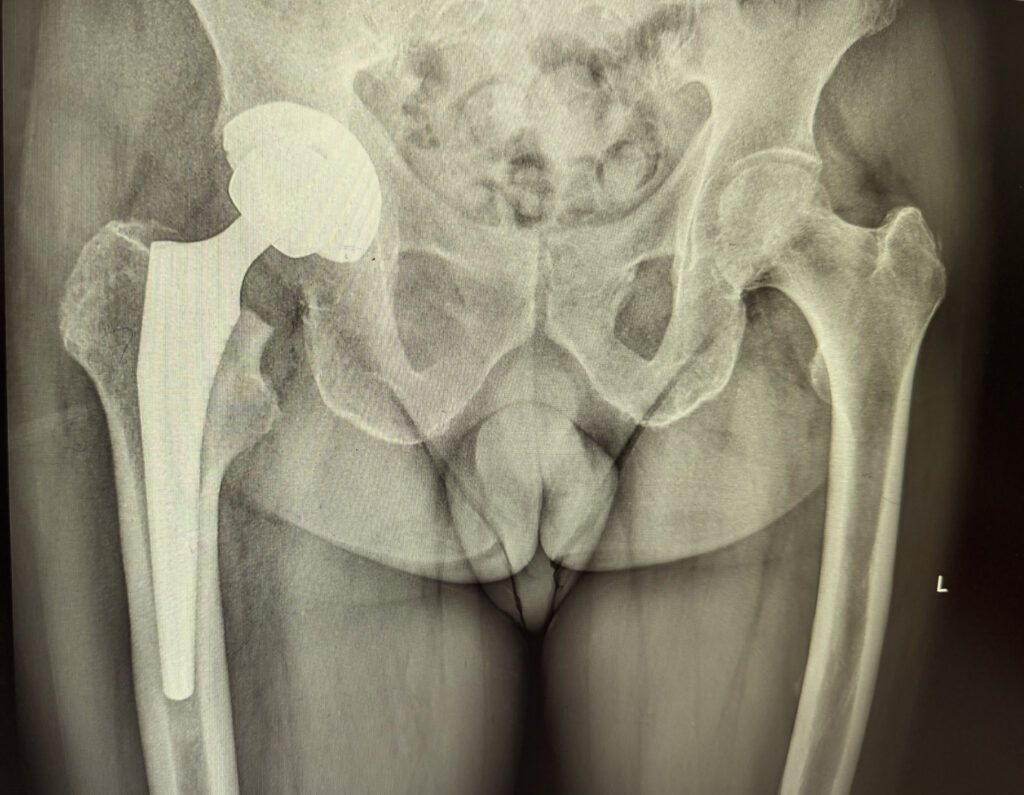

Radiografie postoperatorie PTS

Operația constă în îndepărtarea suprafețelor articulare afectate (capul femural și acetabulul) și înlocuirea lor cu componente artificiale care imită anatomia normală a șoldului.

- Pregătirea acetabulului (șoldul bazinului) și montarea unei cupe metalice în care se fixează un insert din polietilenă sau ceramică.

- Pregătirea canalului femural și montarea unei tije femurale metalice pe care se fixează un cap sferic (metal sau ceramică).

Toate componentele sunt biocompatibile și pot fi fixate cu ciment ortopedic (în cazurile cu densitate osoasă scăzută) sau fără ciment (prin integrare biologică).